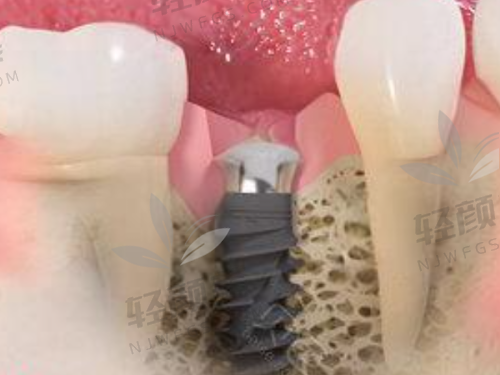

接着,罗医生给我介绍了瑞典Nobel pcc种植牙的优势,比如它的表面处理技术能促进骨结合,让种植体更稳固;而且它的设计特别合理,能更好地模拟天然牙齿的功能。他还给我看了特别多之前患者的实例,成效都特别好。我听了之后特别心动,就决定在这里做种植牙了。

种植体植入后需要一段时间的愈合期,在这段时间里,我每隔一段时间就去北京维乐口腔复查。罗医生每次都仔细检查我的种植体愈合情况,还根据我的修复情况调整护理方案。愈合期大概过了三个月,罗医生说我的种植体已经和牙槽骨结合得良好了,可以安装牙冠了。

安装牙冠的过程特别简单,也没有什么疼痛感。罗医生给我选择了和我其他牙齿颜色特别接近的牙冠,安装好之后,我照镜子一看,哇塞,就跟自己的真牙一样,一点都看不出来是种植牙。而且吃东西的时候也特别给力,再也不用担心咬不动东西了。